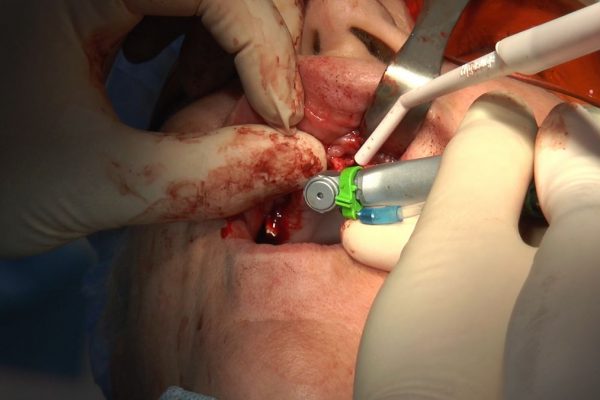

W ostatni weekend czerwca 2018 roku kursanci II Sezonu Preludium Implantologii odbyli piątą, finałową sesję, która w całości podporządkowana była praktyce. W ciągu dwóch dni zabiegowych Lekarze uczestniczący w szkoleniu przeprowadzili szereg zabiegów pod kierunkiem dr n.med. Violetty Szycik. Wszczepili 17 implantów oraz przeprowadzili ekstrakcje i zabiegi regeneracyjne kości. Zabiegi były wykonywane także w sedacji dożylnej z udziałem specjalisty anestezjologii i intensywnej terapii dr Jolanty Grzybowskiej. Preludium implantologii to nowy program edukacyjny dla adeptów implantologii stomatologicznej, którego celem jest wprowadzenie do implantologii poprzez pozyskanie wiedzy w szerokim zakresie i uwzględnieniem szczegółów mających decydujące znaczenie dla powodzenia leczenia implantologicznego. Ale tak jak wszystkie szkolenia w Instytucie Vivadental, w tym wiodące Practiculum Implantologii, zorientowane jest na praktyce i samodzielnym wykonywaniu zabiegów pod kierunkiem Mentora. To najlepsza edukacja w medycynie zabiegowej, a zarazem najlepszy start do implantologii.